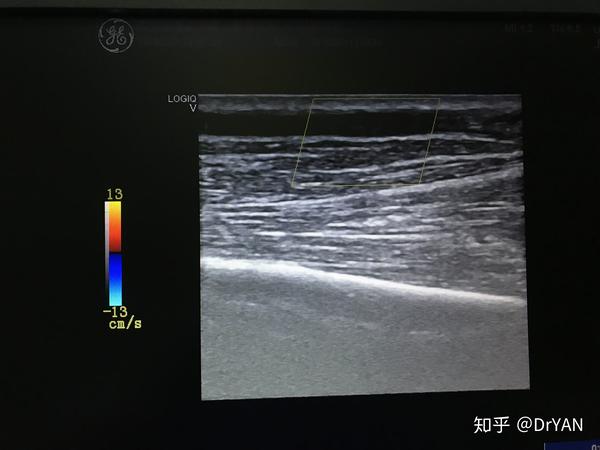

近吻合口头静脉内径6mm.决定从近吻合口头静脉限流.

图片尺寸1250x1000